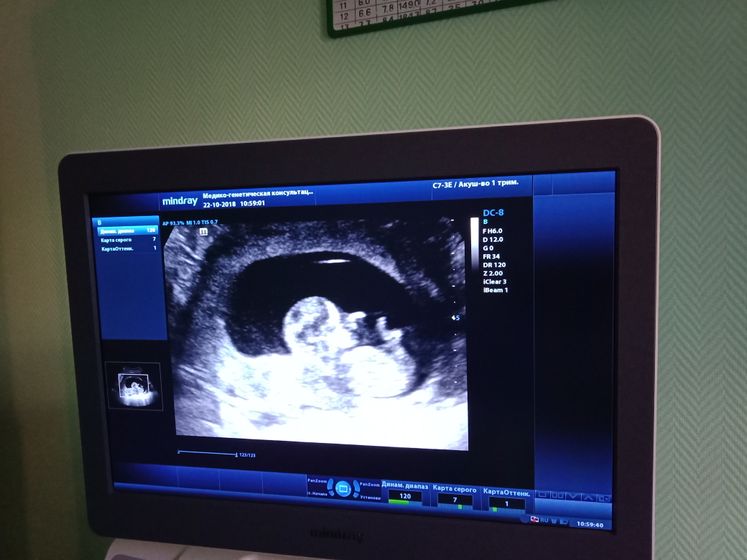

Всем привет! 22 октября должен был быть первый скрининг, но мне сказали что срок ещё маленький и отправили домой. Сделали узи, ктр 46 мм, кроха развивается по сроку, но для замеров скрининга малыш ещё маленький, сказали приходить 1 ноября как подрастёт малыш. По анализу крови поталогий не выявлено. Ну и фото с узи, что в первую беременность что сейчас делаю фото всех узи ?